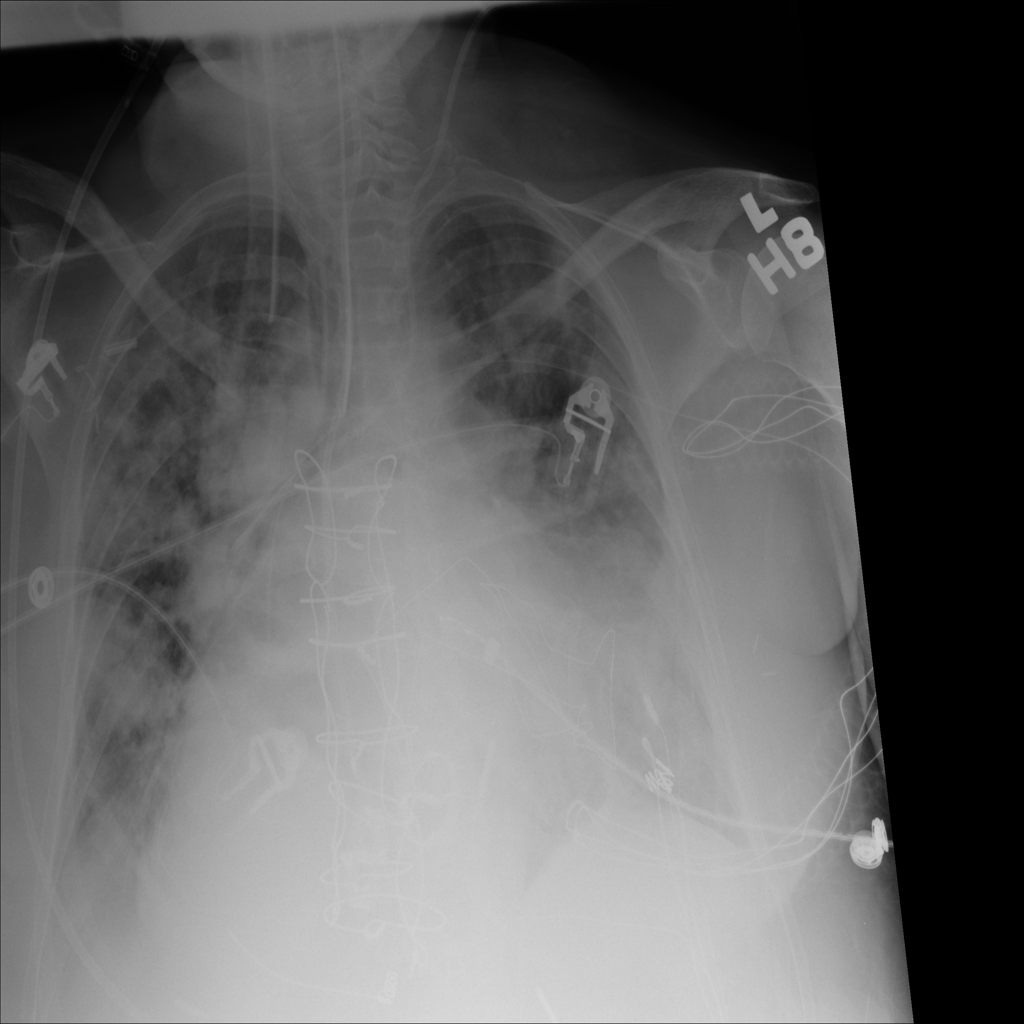

PAT-3384 · IMG-021Cardiomegaly

PAT-3384 · IMG-021

AP